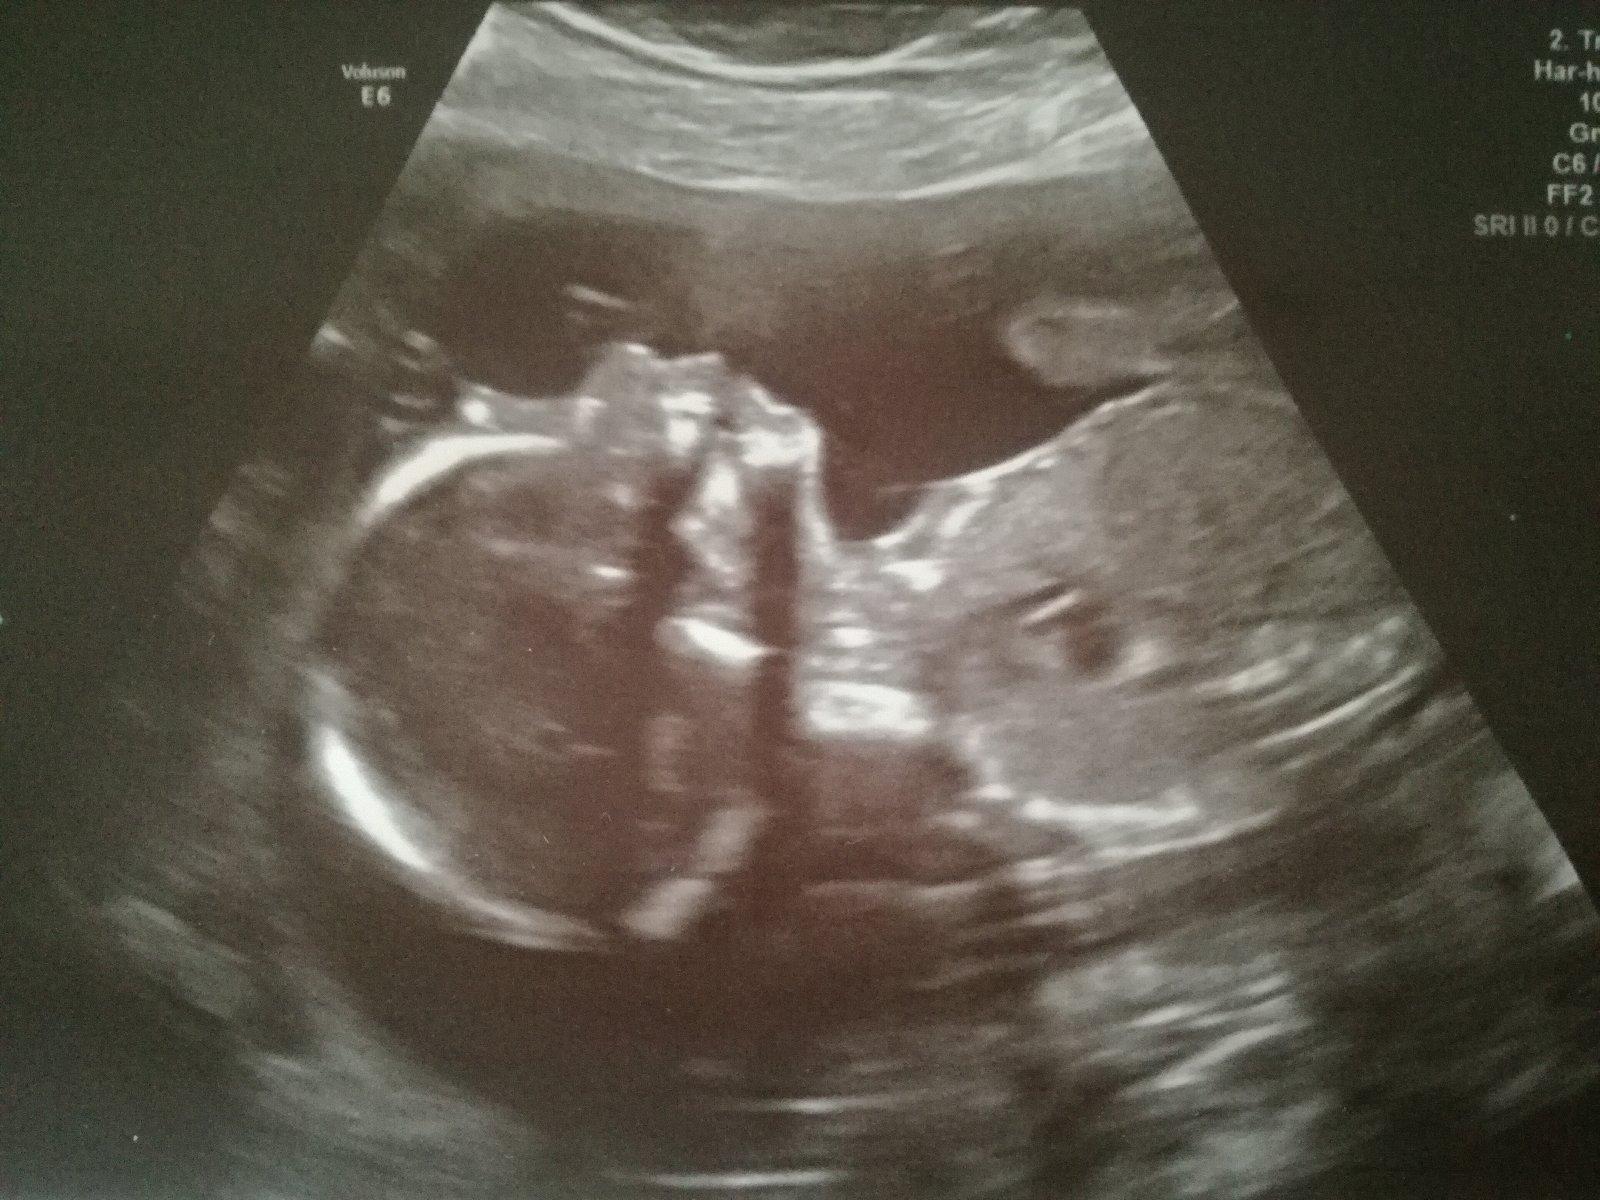

@fonamor Čauky tak snad ta dlouhá stimulace k něčemu bude a chytnou se aspoň 4.Myslím na tebe a držím pěsti štěstí 😉My mame za sebou druhý screening v Heliosu potvrzena 👧 a hlavne zdravá.Přikládám fotečku.Vybavicku zacnu pořizovat teďka uz se na to těším 😀.Tak ahojda a davej o sobe info 😘